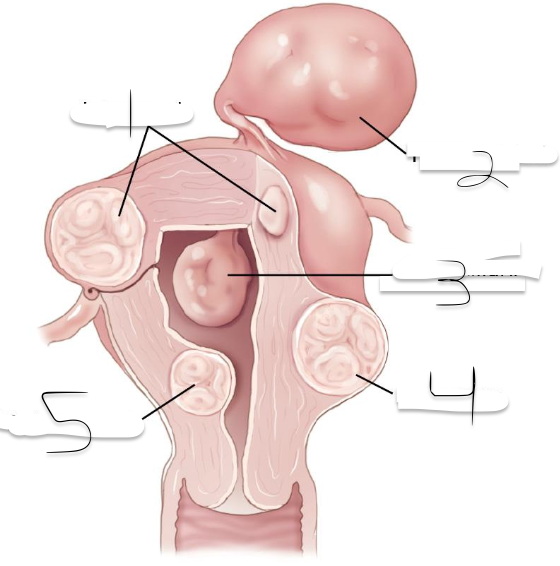

1?

Intramural

2?

Pedunculated

3?

Intracavitary

4?

Suberous

5?

Submuscosal